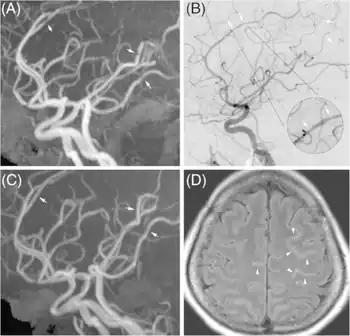

Reversible cerebral vasoconstriction syndrome a) Multifocal vasoconstriction b) anterior, middle, and posterior cerebral arteries c)follow-up indicated significant interval resolution of lesion d) linear hyperintensity lesions in the sulci of frontal lobes

RCVS is diagnosed by detecting diffuse reversible cerebral vasoconstriction.[2] Catheter angiography is ideal, but computed tomography angiography and magnetic resonance angiography can identify about 70% of cases.[2] Multiple angiographies may be necessary.[2] Because other diseases (such as atherosclerosis) have similar angiographic presentations, it can only be conclusively diagnosed if vasoconstriction resolves within 12 weeks.[2]